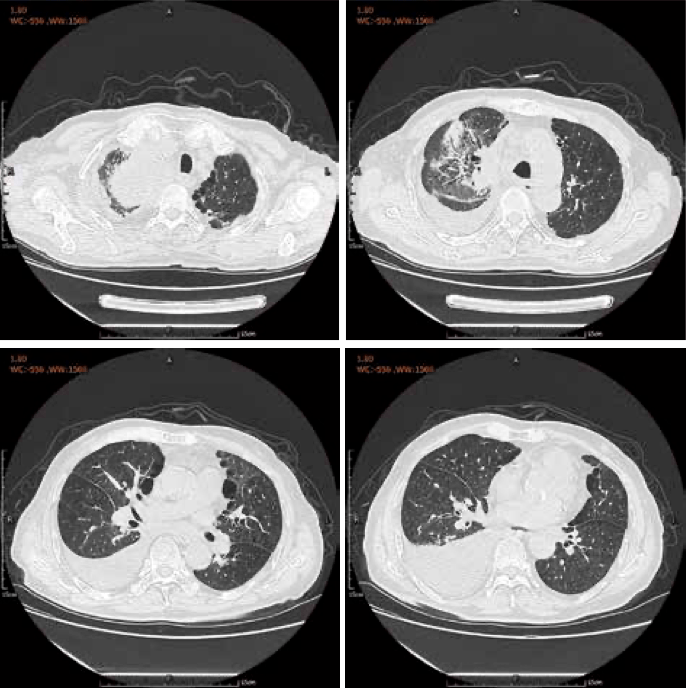

每日技能病例分析之肺癌